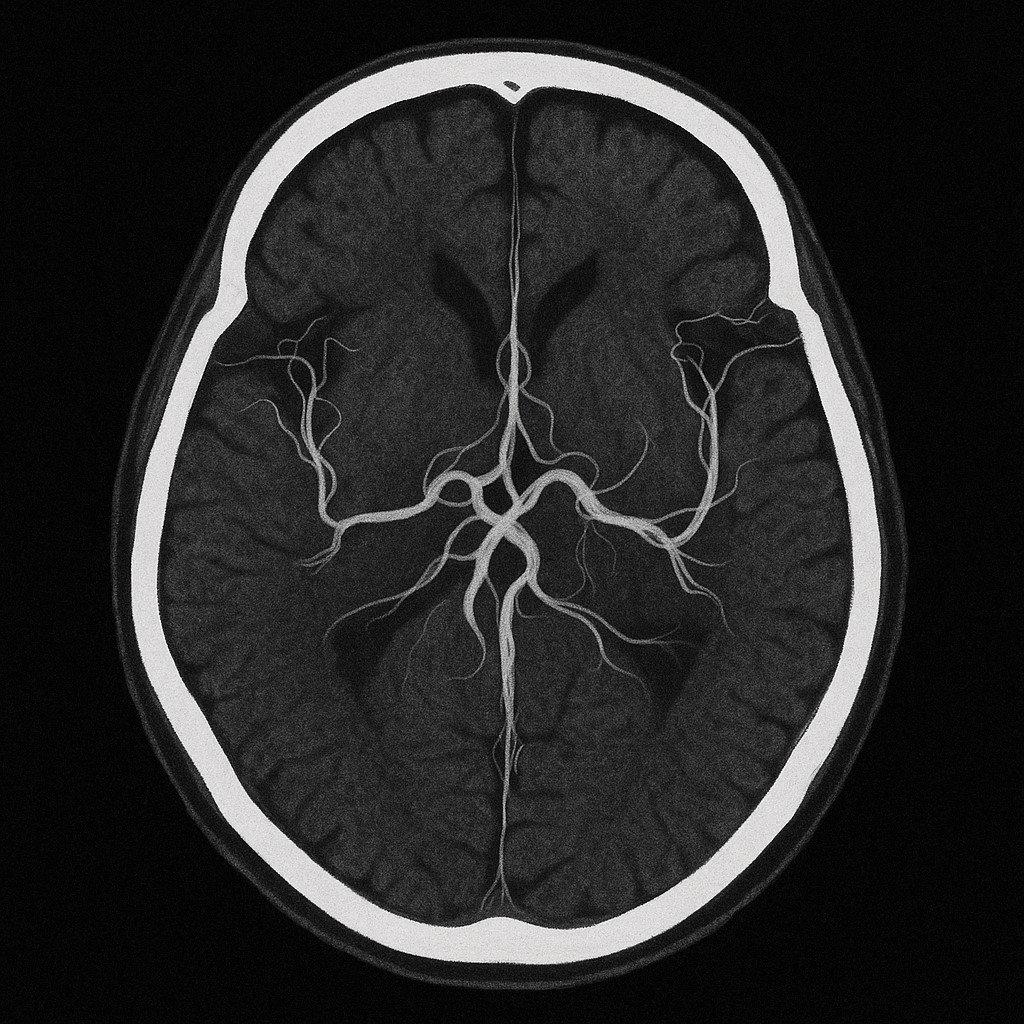

뇌졸중은 뇌에 혈류 공급이 차단되거나 혈관이 터지면서 뇌조직이 손상되는 병이에요. 크게 **허혈성(뇌경색)**과 **출혈성(뇌출혈)**으로 나뉘며, 발병 원인은 고혈압, 당뇨, 고지혈증, 심장질환 등이 있어요.

- 응급치료 골든타임: 뇌졸증 발병 후 3시간 이내, 특히 4.5시간 이내에 병원에 도착해 혈전용해제(알티플라제, tPA 등)를 투여하면 혈류 회복 가능성이 높아져요.